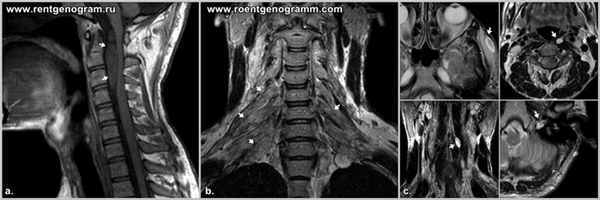

Пилоцитарная (пилоидная) астроцитома — опухоль детского возраста, характеризуется относительно «отграниченным» характером роста (в отличие от диффузных астроцитом) и имеет характерные особенности локализации, морфологии, генетического профиля и клинического течения. Относится к самой низкой (1-й степени злокачественности по классификации ВОЗ для опухолей ЦНС) и имеет наиболее благоприятный прогноз. Чаще встречается в возрасте до 20 лет. Наиболее частая локализация — мозжечок, зрительные пути, ствол мозга. Клиническая картина характеризуется очень медленным нарастанием как фокальной (в зависимости от локализации опухоли), так и общемозговой симптоматики с хорошей адаптацией организма. Особенно характерно медленное нарастание окклюзионной гидроцефалии при опухолях мозжечка и ствола мозга. Диагностика. Опухоль имеет характерную КТ и МРТ семиотику, что позволяет вместе с клинической картиной поставить диагноз до операции. Стандартом предоперационного обследования таких больных является проведение МРТ с контрастным усилением. Лечение хирургическое, цель операции — «тотальное удаление» опухоли, что часто невозможно из-за локализации (ствол мозга, гипоталамус). Прогноз. Выживаемость больных часто составляет более 10–15 лет, в связи с чем точных значений по выживаемости не существует из-за трудностей с анализом столь длительного катамнеза. Примечание. Среди пилоидных астроцитом (чаще гипоталамических) имеется небольшая подгруппа опухолей с выраженным локально «инвазивным ростом» и склонностью к метастазированию по субарахноидальным пространствам.